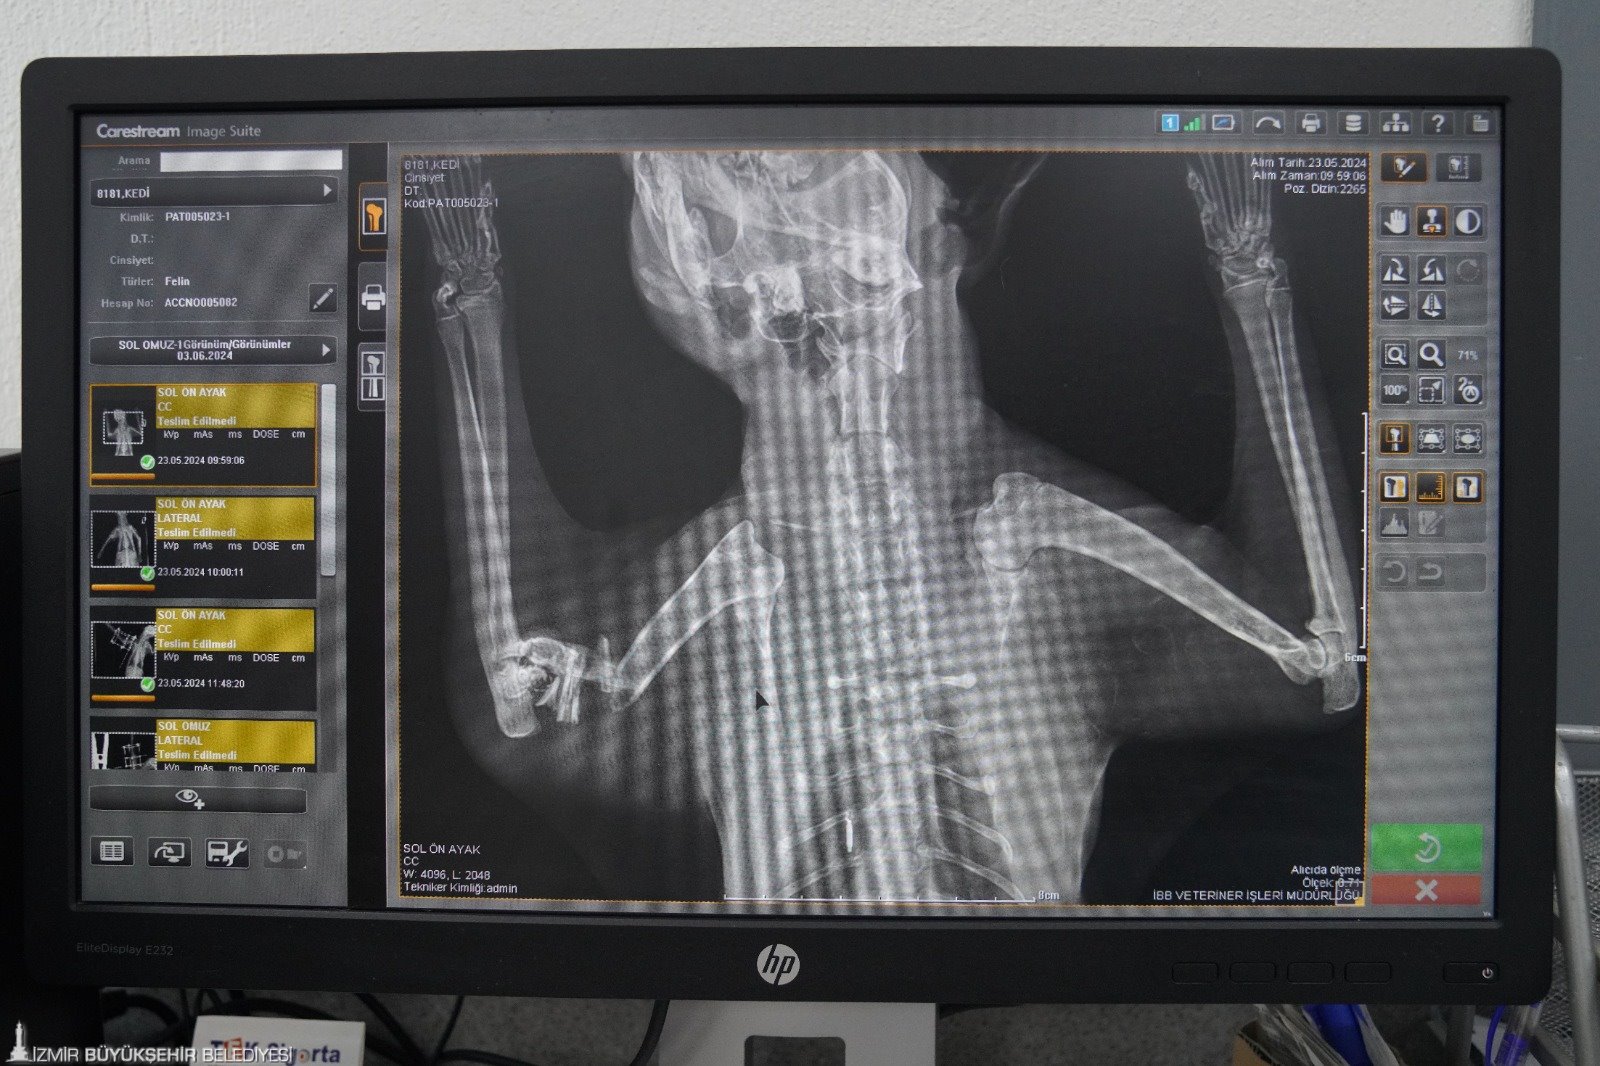

İzmir Büyükşehir Belediyesi Veteriner İşleri Halk Sağlığı Dairesi Başkanlığı Veteriner İşleri Şube Müdürlüğü ekipleri, sahipsiz canların hayatına dokunuyor. Hayvanların bakım ve tedavilerini yapan ekipler zorlu operasyonlara da imza atıyor. PAKO Sokak Hayvanları Sosyal Yaşam Kampüsü'nde gerçekleştirilen başarılı bir cerrahi operasyonun ardından sahipsiz bir kedinin bacağı kurtarıldı. Dost canlısı tavırlarıyla herkesin sevgisini kazanan kediye veterinerler Balım ismini verdi.

Özel aparatla sabitlendi

Ameliyat hakkında bilgi veren Veteriner Hekim Mehmet Uysal, ortopedi biriminde kedinin bacağının durumunu tespit ettiklerini belirterek, “Bacağının ciddi şekilde parçalandığını gördük. Burada sağlığına kavuşması için hemen gerekli cerrahi tedaviyi uyguladık. Bacağında parçalanan kemikleri özel bir aparatla sabitledik. Güvenli bir yöntem olduğu için bunu tercih ettik. Kedimiz 25 gündür bu şekilde tedavi altında. Bir süre sonra bu taktığımız aparatın kırıklar üzerindeki etkisine bakacağız. Bacak iyileşmiş olursa çıkaracağız. Şu anda sağlığı ile alakalı bir problemi yok. Keyfi yerinde. Bacağını nasıl kullanacağını öğreniyor diyebilirim” diye konuştu.